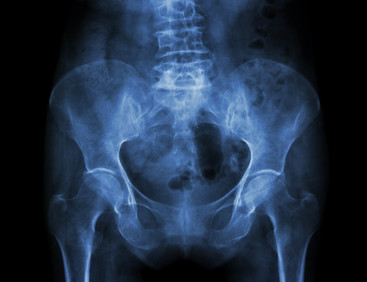

• Røngtenbilde av osteperosepasient. Bilde hentet fra colourbox.com